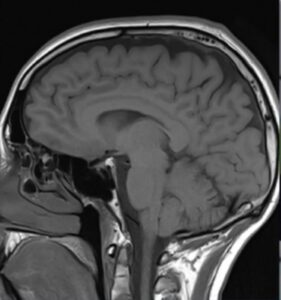

Genes linked to common brain disorder identified

brain